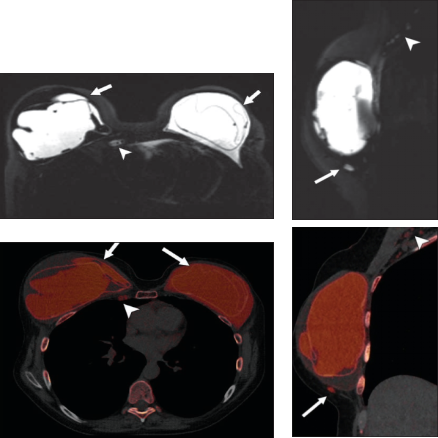

评估骨髓浸润活性

双能量硅图:硅胶假体破裂